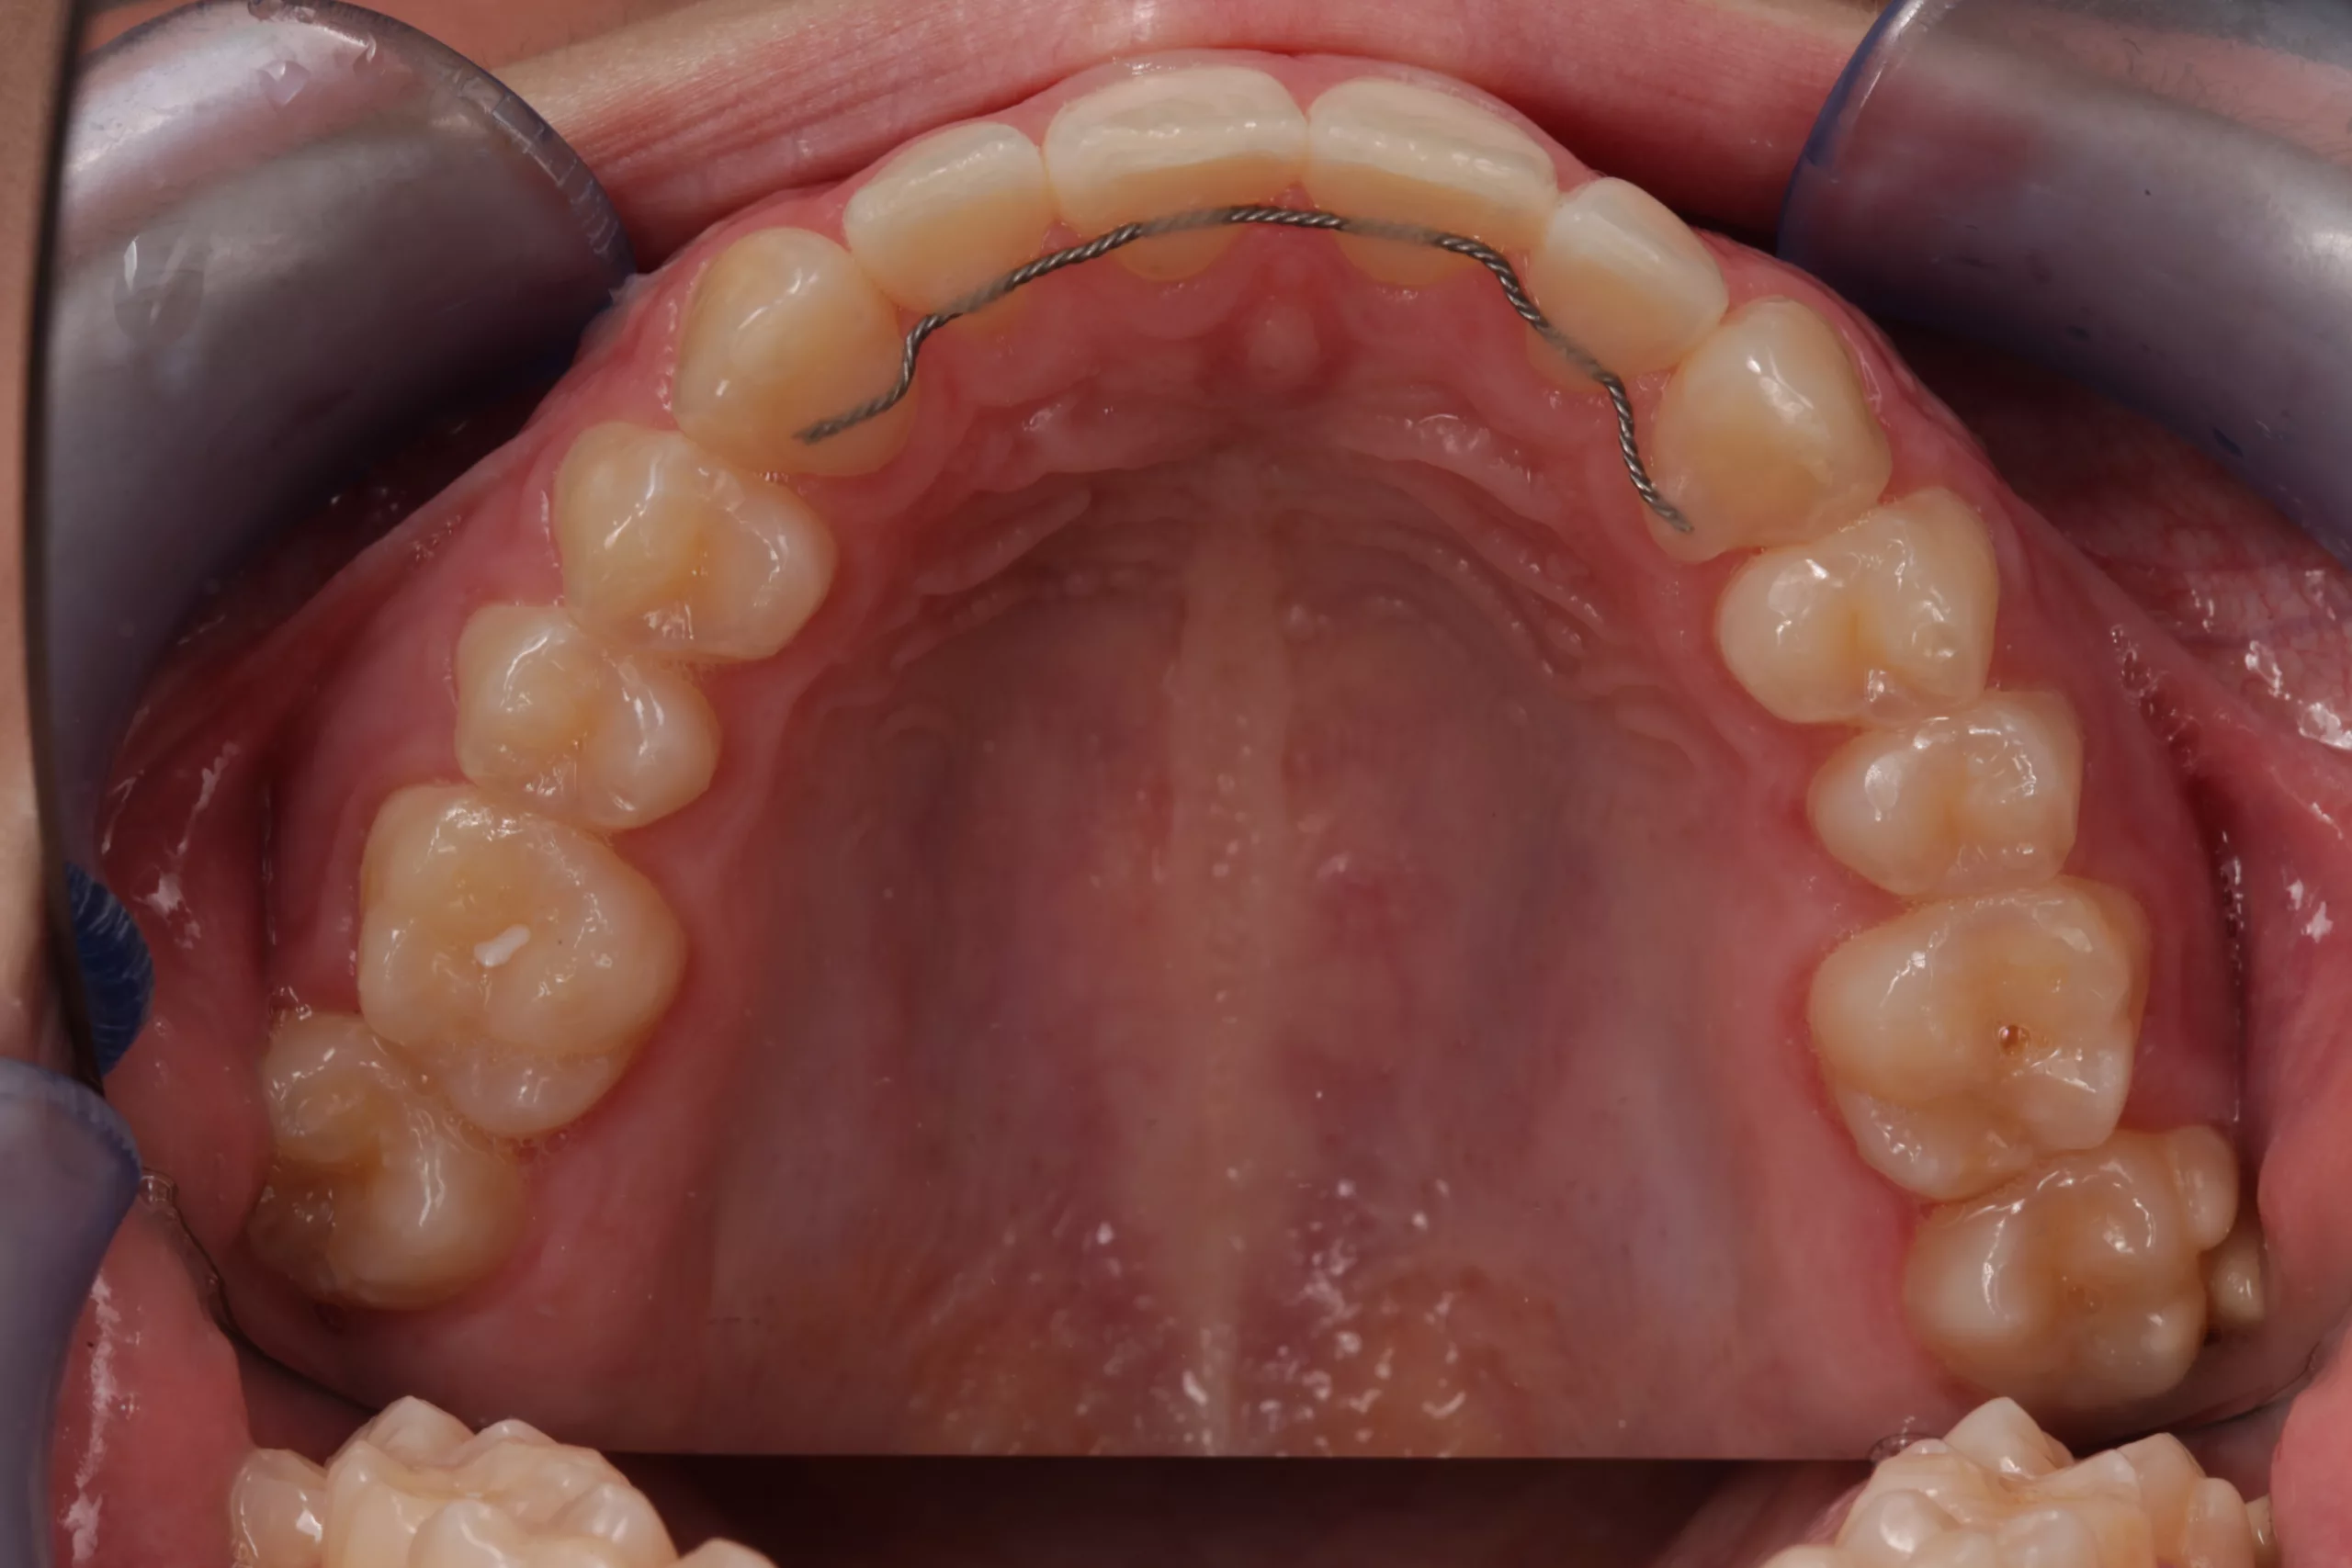

Eine 17-jährige Patientin stellte sich nach kieferorthopädischer Vorbehandlung alio loco und bereits erfolgter Lückenöffnung regio 32, 42 bei Nichtanlage 31, 41 in der Klinik für Zahnärztliche Prothetik und Biomaterialien, Zentrum für Implantologie des Universitätsklinikums Aachen mit dem Wunsch nach einer Lückenversorgung vor (Abb. 2-4). Die Lücken wurden mithilfe eines herausnehmbaren Zahnersatzes (Interimsprothese) offen gehalten. Nach aktiv- kieferorthopädischer Therapie sollten mindestens 6 bis 8 Wochen als Retentionszeit vor der definitiven, festsitzenden prothetischen Versorgung kalkuliert werden [7].

Okklusion und Artikulation können nun überprüft und ggf. angepasst werden. Abschließend folgt die Instruktion des Patienten zur effizienten Reinigung im Bereich der Adhäsivbrücke. Eine Situationsabformung mit anschließendem Situationsmodell und die fotografische Dokumentation des klinischen Ergebnisses helfen bei den Nachsorgesitzungen zur Kontrolle etwaiger Veränderungen der Pfeilerzahnstellung (Abb. 13- 15).